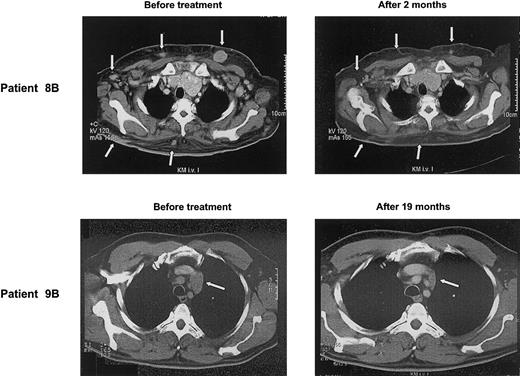

A more detailed description of the patients achieving an objective tumor response gives an impression of how γδ T-cell–mediated immunotherapy might operate: patient 9B with a follicle center lymphoma had relapsed despite high-dose chemotherapy. After 3 cycles of pamidronate/IL-2, CT scan revealed insignificant changes of most lymph nodes, except one that had increased in size. Biopsy of this lymph node revealed a predominant fibrosis with only small numbers of lymphoma cells left. Thereafter, tumor mass steadily declined and, after 19 months of treatment, a PR has been reached (Figure 3).

Clinical response to treatment. CT scans of patients 8B and 9B before and after several cycles of pamidronate/IL-2 therapy show regression of skin metas tases and mediastinal lymph node (arrows), respectively.

Patient 8B had relapsed with a follicle center lymphoma and developed multiple subcutaneous manifestations in addition to multiple lymph node involvement. After the start of pamidronate/IL-2 treatment, the subcutaneous nodules rapidly disappeared (Figure 3), whereas nodal manifestations regressed slowly. Two months later, treatment was stopped because of noncompliance of the patient.